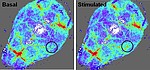

My group is interested in the regulation of cerebral blood flow at the blood brain barrier (BBB) and in the distinct roles of the involved cells types. The BBB is formed by vessels and consists of the basement membrane and cells, which have special properties leading to a very tight and highly organized structure at the interface between blood and brain.

In a healthy brain, the BBB prevents neural tissue from the invasion of pathogens, the infiltration of immune cells and extravasation of serum proteins. In addition, brain cells have a high demand for glucose, oxygen, and other factors, coming from the blood. The perfusion with blood is tightly regulated in terms of time and localization. In this process different cell types, including neurons, astrocytes, pericytes, smooth muscle cells, and endothelial cells, are activated and all of them are able to influence the kinetics and amplitude of perfusion. If the communication between these cells is dysregulated as in stroke, dementia, diabetes, or obesity, also vascular reactivity is altered.

We are interested in intercellular connections, especially in those that involve endothelial cells, and in the effects of endothelial dysfunction on related brain functions. For this purpose we are using state-of-the-art technologies like two-photon microscopy, tissue-specific knockout animal models, and virus-mediated gene transfer.